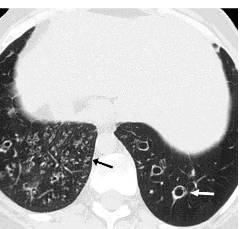

尤文肉瘤:右肺下叶后段结节沿肺动脉周边分布形成树芽征

4.先天性疾病

在囊性纤维化这种常染色体阴性遗传病中,树芽征可能是一个早期征象、这主要是由于细支气管内有大量的黏性分泌物停留所致。Kartagener综合征中,HRCT表现包括小叶中心结节影(树芽征)。

先天性囊性纤维化:高分辨率CT扫描显示支气管扩张、支气管壁增厚和弥散性树芽征